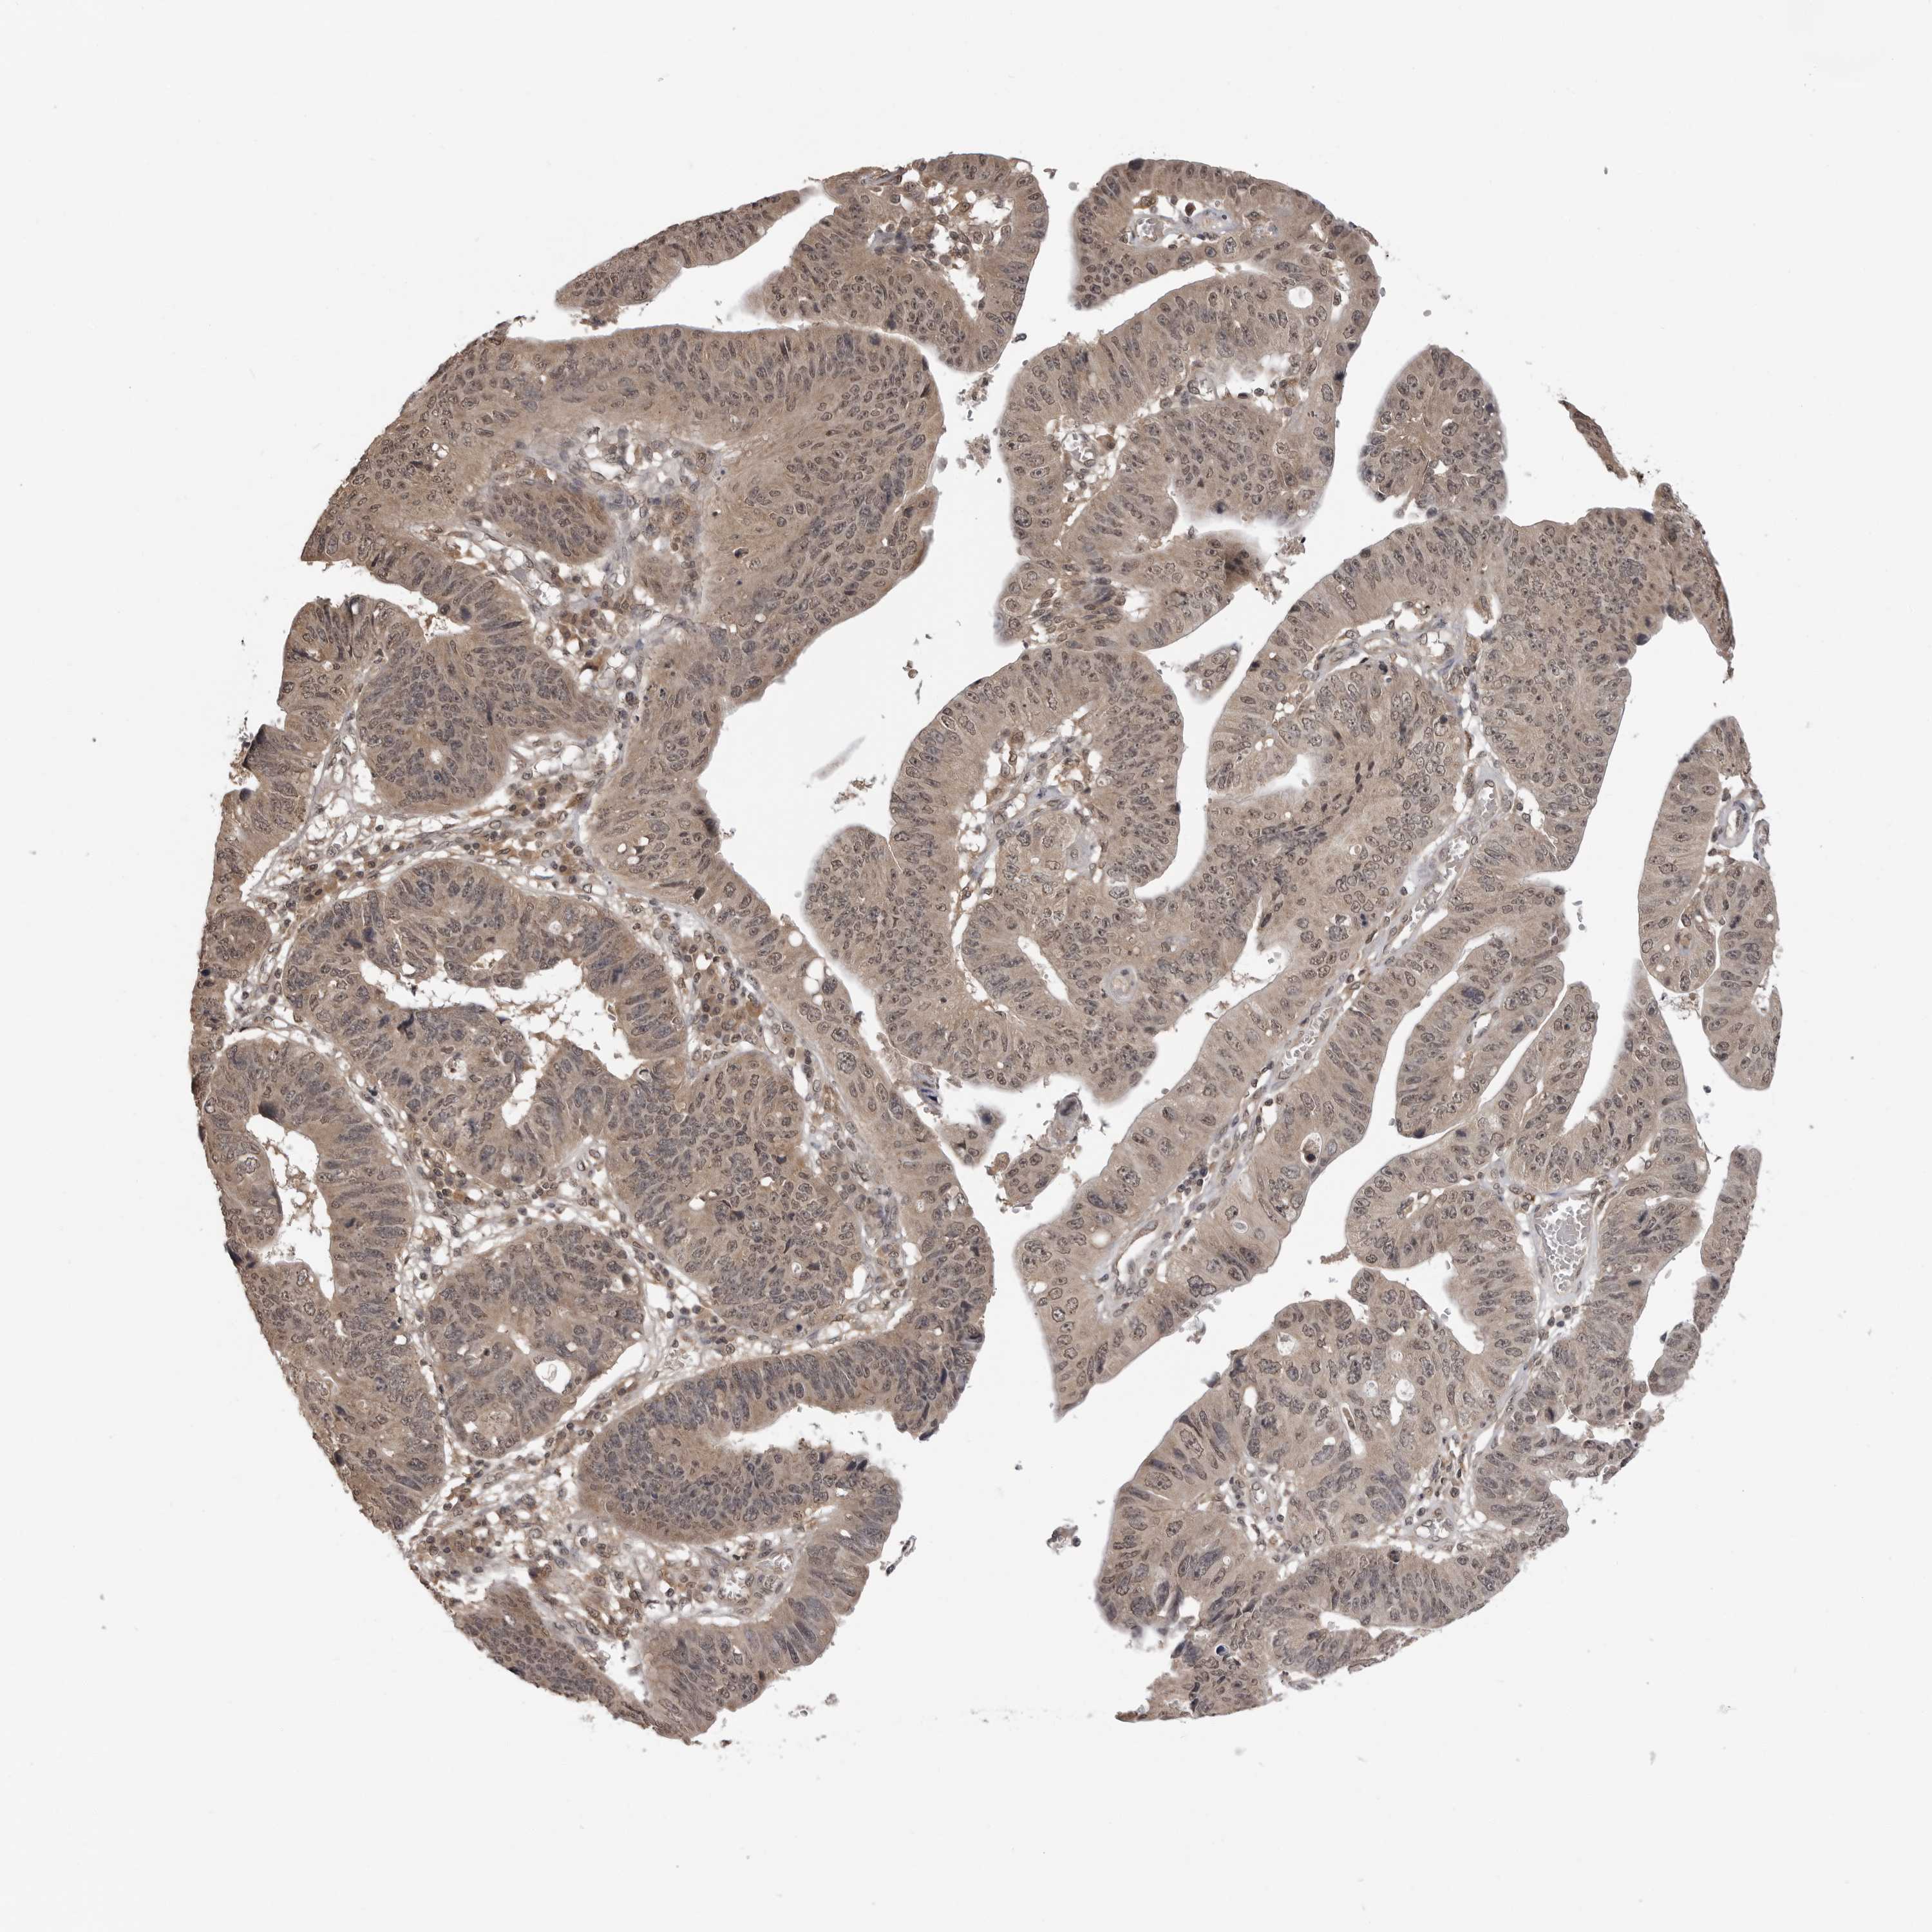

STOMACH CANCER - Protein expressioni

A mouse-over function shows sample information and annotation data. Click on an image to view it in a full screen mode. Samples can be filtered based on level of antibody staining by selecting one or several of the following categories: high, medium, low and not detected. The assay and annotation is described here.

Note that samples used for immunohistochemistry by the Human Protein Atlas do not correspond to samples in the TCGA dataset.

Antibody stainingi

Antibody staining in the annotated cell types in the current human tissue is reported as not detected, low, medium, or high, based on conventional immunohistochemistry profiling in selected tissues. This score is based on the combination of the staining intensity and fraction of stained cells.

Each image is clickable and will lead to virtual microscopy that enables deeper exploration of all samples and also displays staining intensity scores, fraction scores and subcellular localization as well as patient and tissue information for each sample.

Antibody CAB025972

Staining

High

Medium

Low

Not detected

Intensity

Strong

Moderate

Weak

Negative

Quantity

>75%

75%-25%

<25%

None

Location

Nuclear

Cytoplasmic/membranous

Cytoplasmic/membranous,nuclear

Adenocarcinoma, NOS